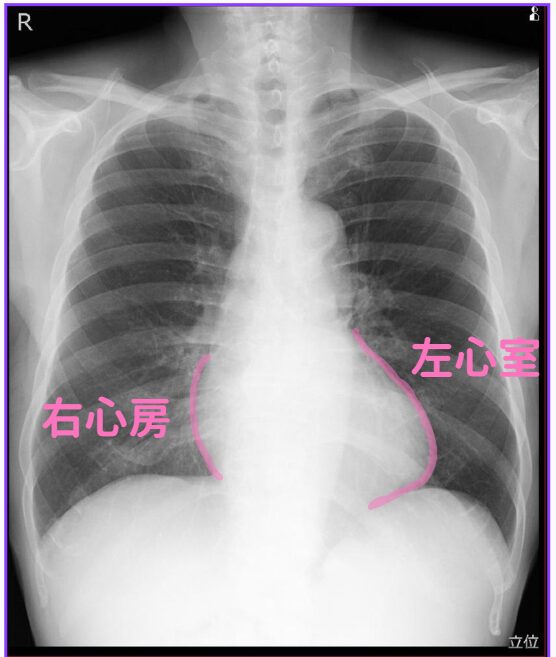

(4)右心房・左心室

心臓はちょっと傾いています。

なので右心房のラインと、左心室のラインが同じくらいの高さになります。

心臓が大きい場合、まず心不全を疑います。

例えば両側胸水貯留を見たとき、心拡大があればうっ血性心不全を疑います。

心拡大がなければ肝硬変からの低アルブミン血症かも知れません。